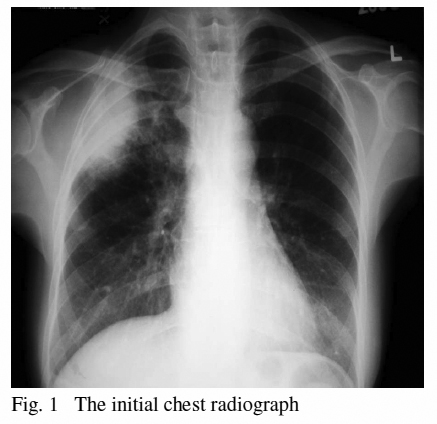

She was a non-smoker; non-drinker and enjoyed her good functional status. Her symptoms were only associated mild weight loss and reduced appetite. In reviewing her symptoms, she denied any dyspnoea, epistaxis, fever or nasal congestion. There was no relevant travel or contact history. On examination she was afebrile and all vital signs were stable. Inspiratory crepitations were noted over her right upper lung field. Initial chest roentgenogram revealed peripherally located right upper lobe infiltrate. (Fig. 1)